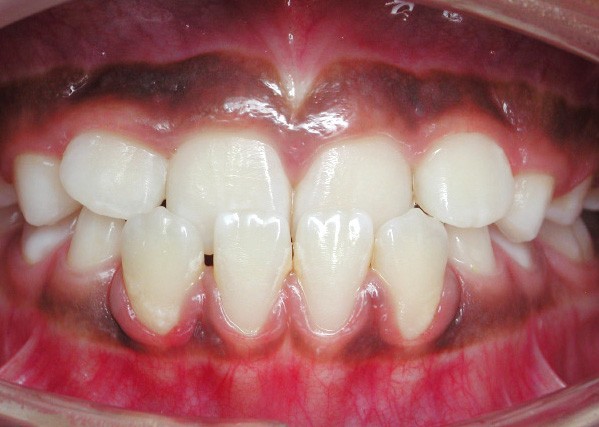

L’omnipraticien est très souvent confronté à cette question lors de sa pratique quotidienne : quel est le bon moment pour adresser les enfants chez l’orthodontiste ? La réponse peut recéler quelques difficultés, car elle est spécifique à chaque enfant. Le temps où il était conseillé d’attendre la denture définitive pour intervenir est révolu : certaines interventions précoces permettent aujourd’hui dans certains cas de raccourcir et de simplifier les traitements orthodontiques. C’est notamment le cas des anomalies transversales, qui sont celles qui sont traitées le plus précocement, dès 6 ans. Ainsi, lors d’anomalie cliniquement évidente, la consultation orthodontique s’impose. Cependant, certaines anomalies sont plus discrètes, et donc plus difficiles à dépister. Une panoramique doit toujours être réalisée en première intention afin de dépister les agénésies. Puis, même en l’absence d’anomalie évidente, il est recommandé d’adresser les enfants chez l’orthodontiste entre 7 et 9 ans : celui-ci sera ainsi à même d’adapter la prise en charge, et surtout l’âge idéal de prise en charge pour chaque patient(fig. 3 et 4).